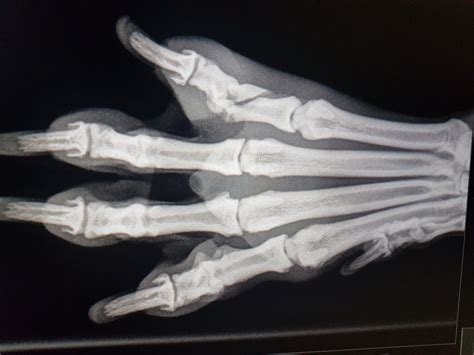

Heeft u het vermoeden dat uw huisdier een gebroken poot heeft, dan is het verstandig om de beweging van de poot te beperken om verdere schade te voorkomen. Probeer uw huisdier te kalmeren. U kunt voorzichtig de poot ondersteunen en in een stabiele positie houden. De dierenarts zal aanvullend onderzoek uitvoeren om de exacte aard en de locatie van de breuk vast te stellen. Er worden röntgenfoto's van de poot gemaakt. Hierop is gedetailleerde informatie over de breuk te zien. Dit helpt de dierenarts om de ernst van de breuk te beoordelen. Ook de locatie van de breuk is belangrijk om te weten. Daarnaast spelen er nog andere dingen mee, zoals bijvoorbeeld hoe oud de breuk is, wat de leeftijd van het huisdier is en of er veel schade is aan de spieren, pezen, gewrichtsbanden, etc. Niet elke breuk is met een röntgenfoto goed te beoordelen, er kan dan een CT-scan nodig zijn.